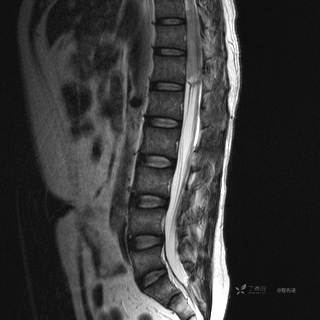

MR

T2